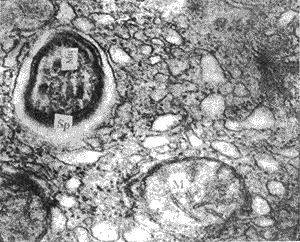

2.2.1 对照组 肝细胞内线粒体丰富,线粒体嵴清晰可见,内质网丰富,在毛细胆管区附近可见一Sp,纳虫泡清晰,纳虫泡周围可见较多粗面内质网、核糖体、及线粒体,Sp内微线体明显(图1)

, http://www.100md.com 图1 对照组肝细胞内线粒体(M),纳虫泡内Sp结构完整,内含微线体(Mn)30000×